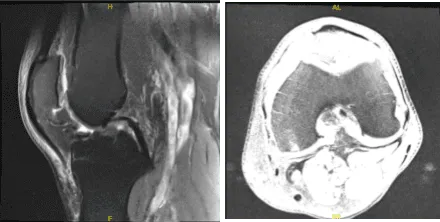

The patient presented MRI results for his left and right knees. For the right, moderate medial compartment arthrosis and a small horizontal tear along the superior articular surface of the posterior horn medial meniscus. There is evidence of previous partial medial meniscectomy.

There is mild lateral and patellofemoral arthrosis. There is a large joint effusion. For the left, Moderate-severe medial knee osteoarthritis with broad full-thickness cartilage loss and bone-on-bone apposition. Complex degeneration and tearing of the medial meniscus. Joint effusion with synovitis/debris.

MRI-3T Right knee non-contrast

MRI-3T Left knee non-contrast